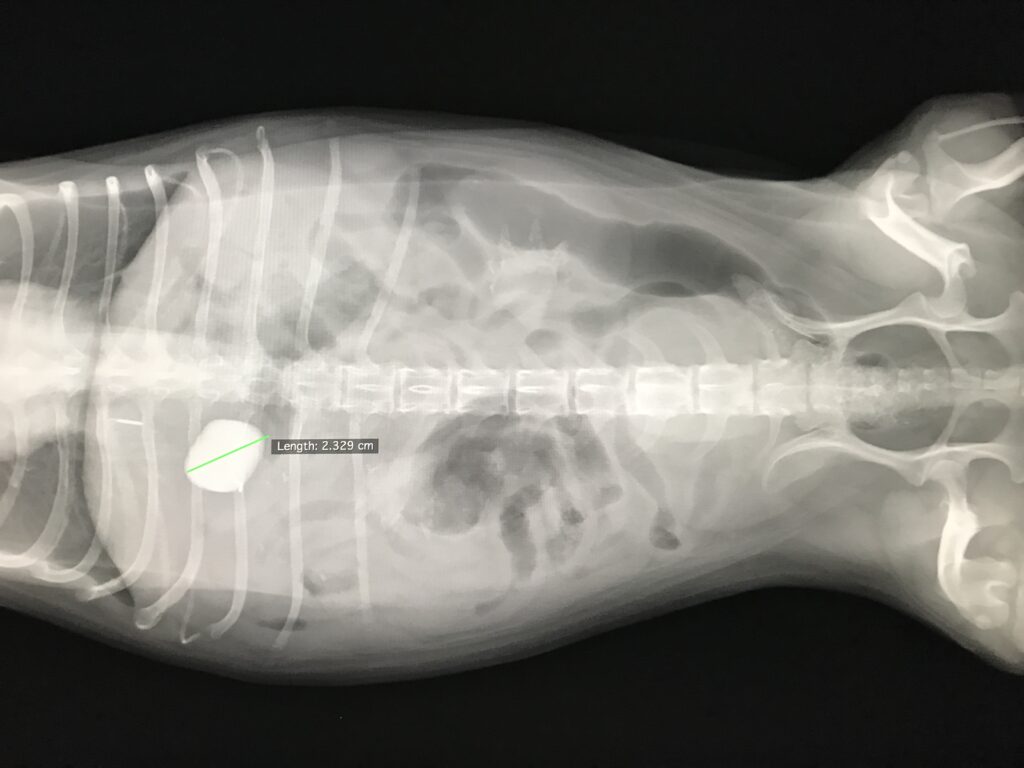

一応レントゲンを撮ると、2cm大の石が写っている・・

この石のせい?よく見ると石と針金状の異物が確認され、その針金が消化管に刺さって痛みを起こしている可能性はあります。ひょっとしたら足腰が痛い可能性もありますが、消化管内異物によって痛みが生じて歩行異常とヨダレが出てるのでは?と判断し、オーナー様に相談の上異物摘出手術を実施しました。

胃内に1辺が2cmほどの石(観賞魚の水槽で水草をくくりつける石?)人工的な石で針金が飛び出ていました。胃内に異物もあったのでそれも取り出しました(最近流行りの立体シール『ドロップシール』が出てきました)。テレビで見てドロップシールの存在は知っていたのですが手術で摘出した際にはプラスチック片だと思いました。ドロップシールは小学校低学年くらいの児童で人気の立体シール(ぷっくりシール)で、透明樹脂で飴玉のように盛り上がった、つやつやした質感が特徴のデコレーションアイテム。文房具店等では売り切れ続出の人気とのこと・・消化管から出てきた立体シールの絵柄などは確認できませんでしたが、当院スタッフによるとドロップシールだろうとのこと。